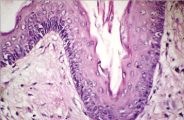

Figure 4. Keratocyst with hyper-keratosis.